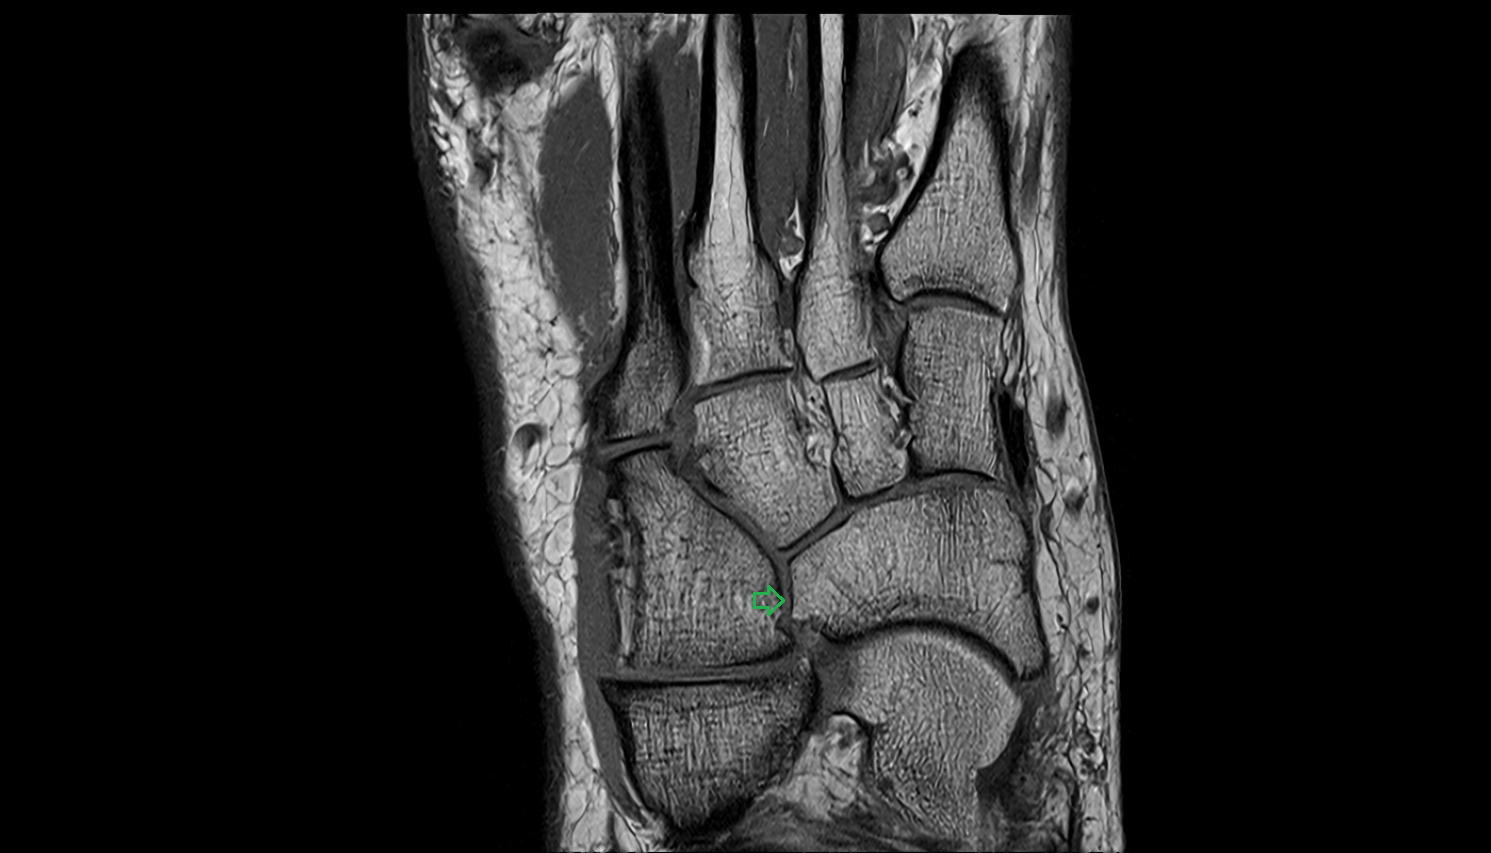

- Talus

- Head of talus

- Body of talus

- Neck of talus

- Posterior talar articular facet

- Calcaneus

- Anterior process of calcaneus

- Sustentaculum tali

- Tuberosity of navicular bone

- Cuboid

- Medial malleolus

- Lateral malleolus

- Ankle joint

- Talocalcaneal joint

- Talocalcaneonavicular joint

- Calcaneocuboid joint

- Lateral cuneiform bone

- Medial cuneiform bone

- Intermediate cuneiform bone

- Navicular bone